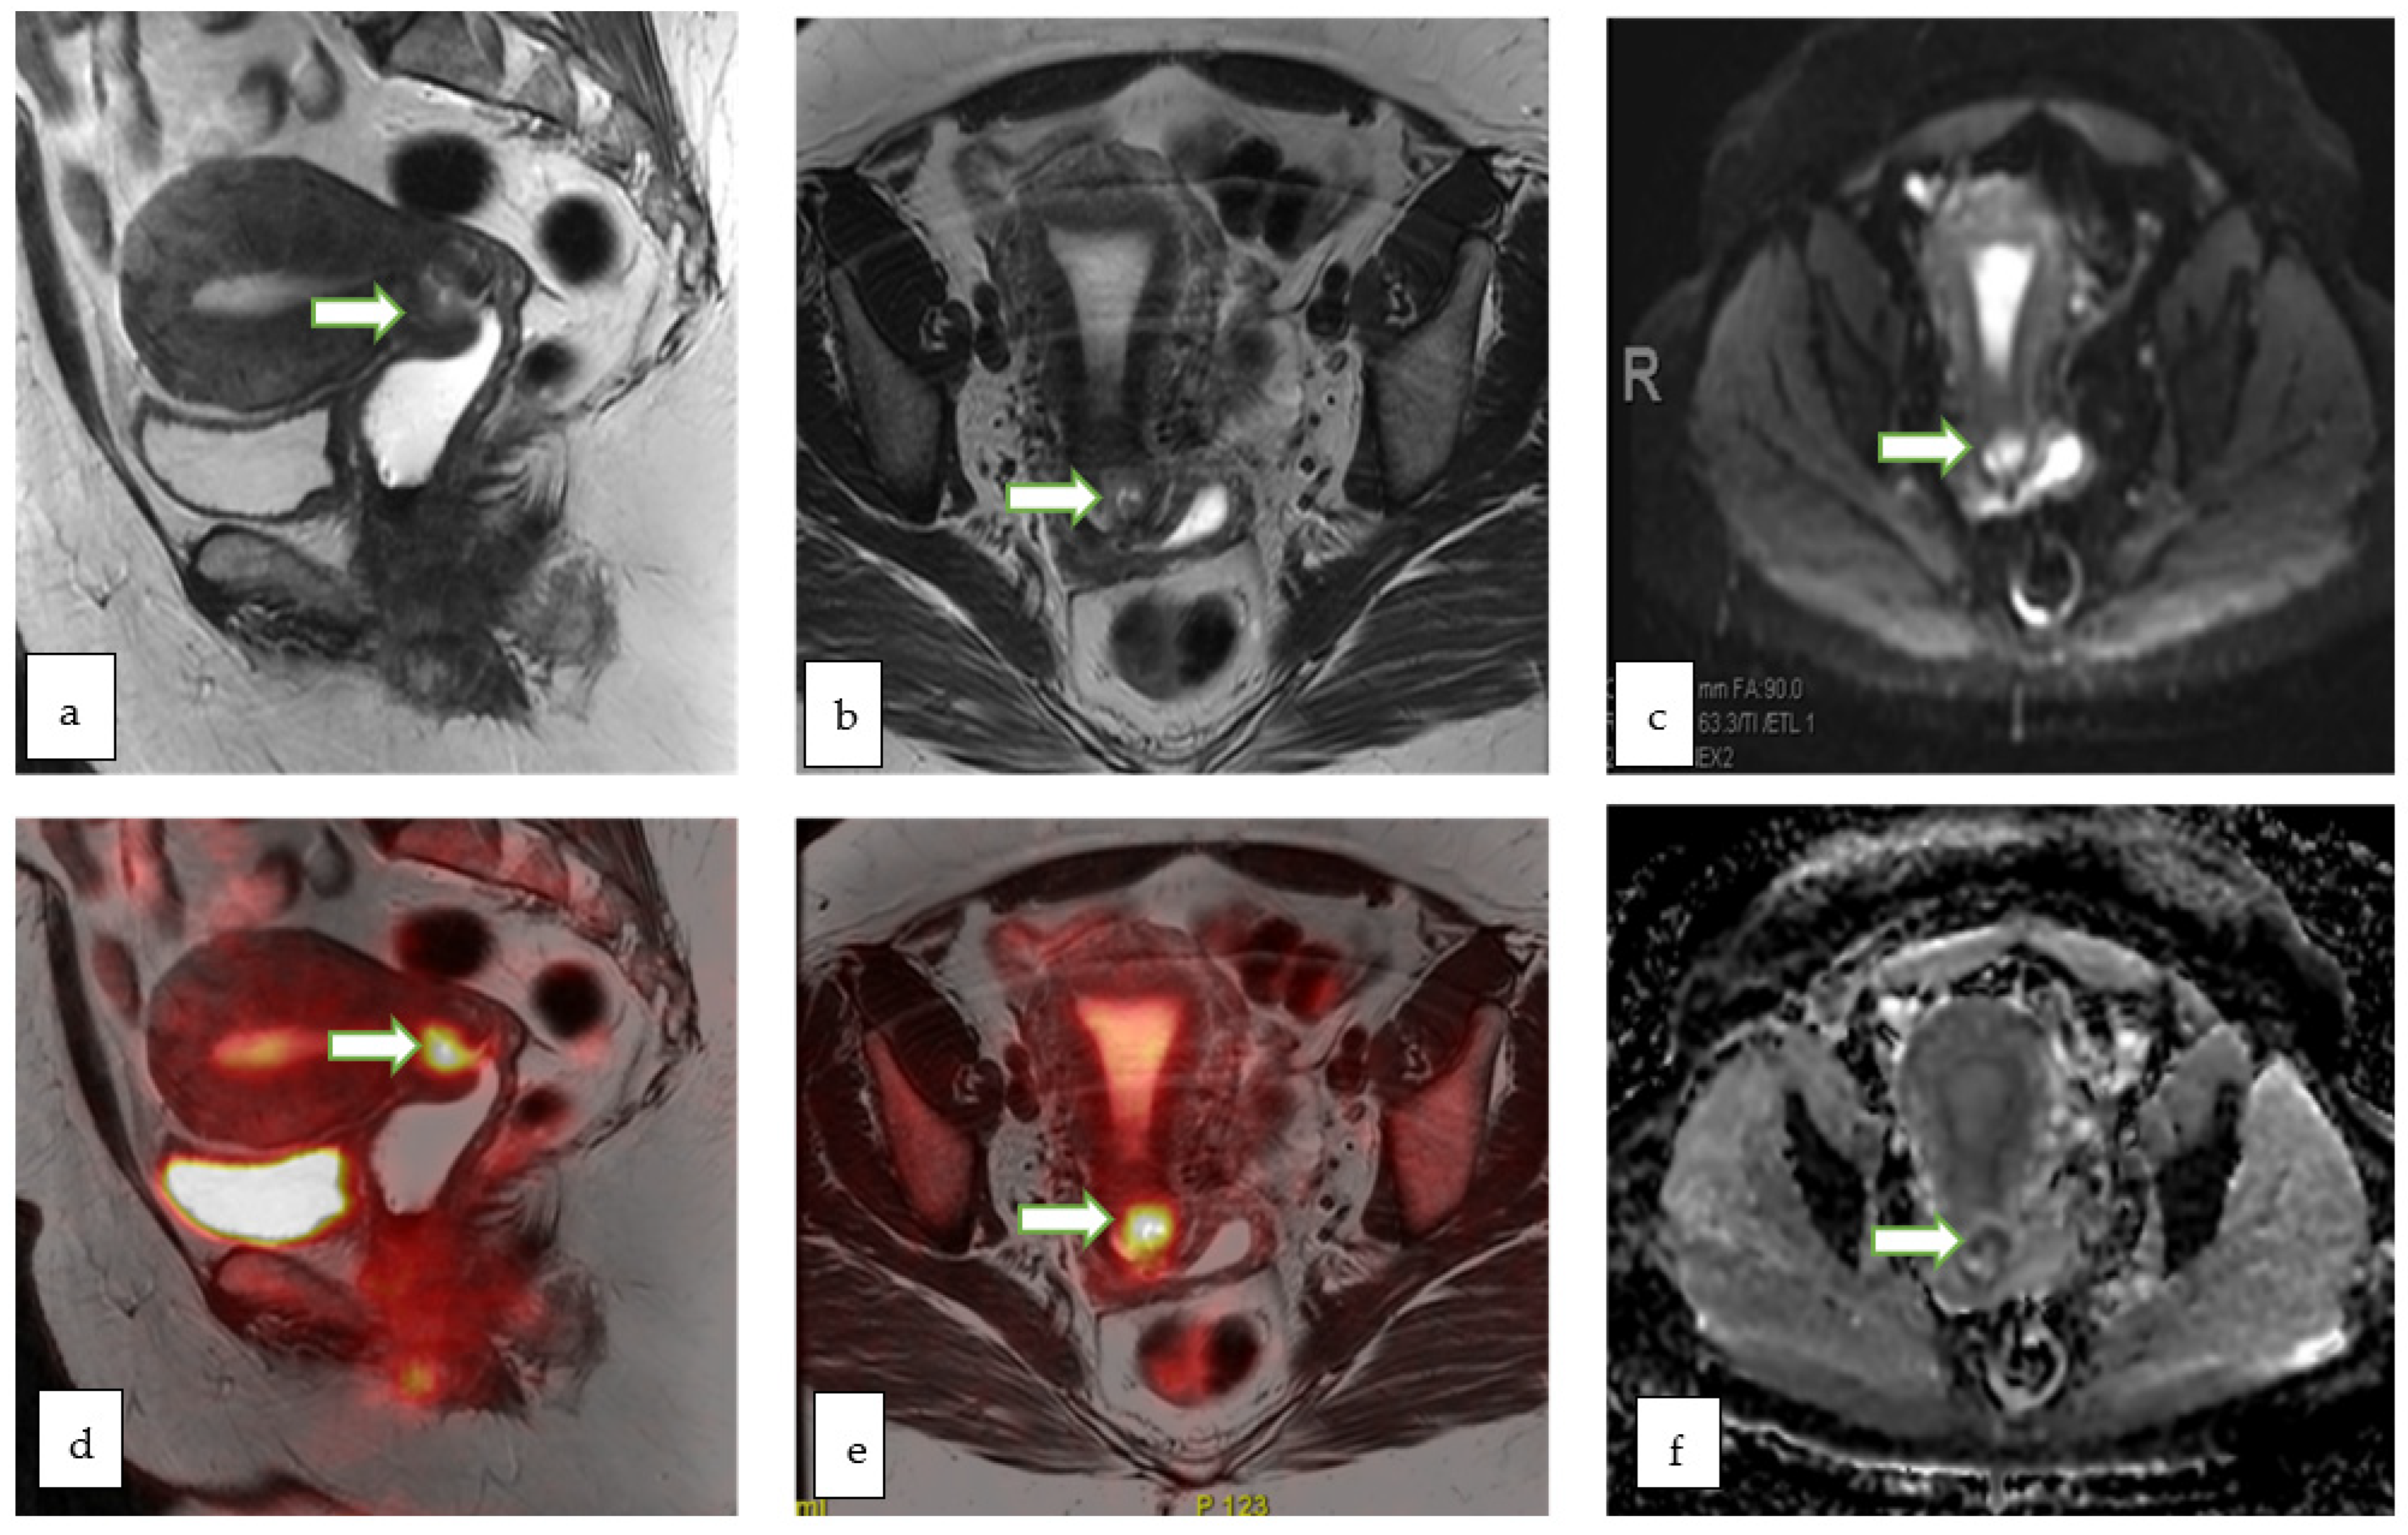

- PET-MRI allows a one-stop assessment of gynecological malignancies, combining the functional and quantitative metabolic data of PET with the high-resolution anatomic and functional imaging properties of MRI. Although it shows promising diagnostic performance, limited data in the literature exists regarding the justification of its high cost compared to separately acquired PET-CT and MRI.